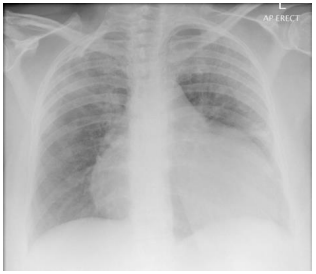

Homem, 60 anos, portador de diabetes mellitus e insuficiência renal crônica em hemodiálise três vezes por semana há dois anos. Na última semana, após faltar a duas sessões de diálise, evoluiu com dispneia aos pequenos esforços e dor torácica pleurítica.

Considerando sua radiografia de tórax (acima), assinale a opção que apresenta um possível achado no seu exame físico.